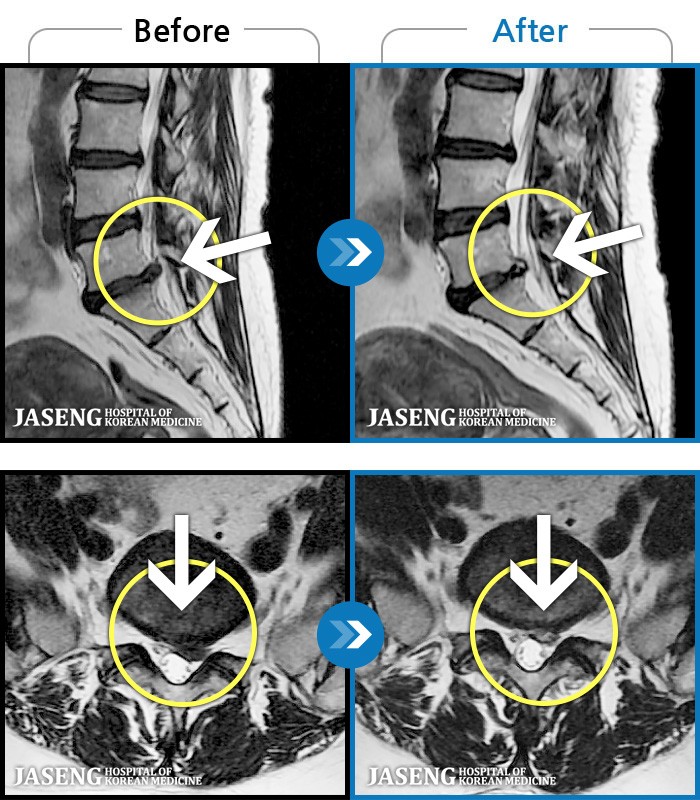

- MRI ġ

MRI ġ

1,237 MRI ũ ʸ Ȯϼ.